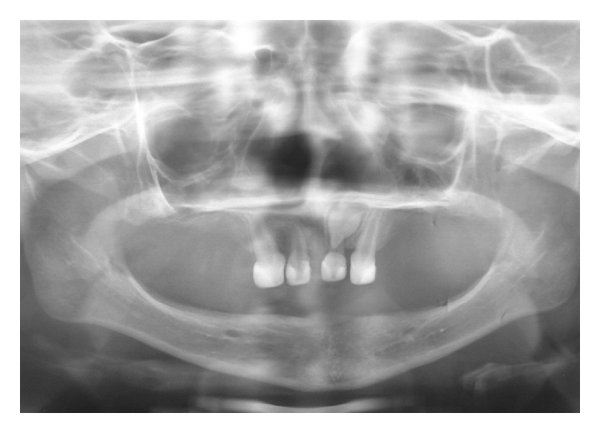

Clinical and radiographical examination revealed a partially edentulous maxilla and a completely edentulous mandible. In the maxilla only the primary maxillary central and lateral incisors were present. The primary maxillary central and lateral incisors had apparently been previously restored using resin strip crowns, because these teeth are often conical in shape in ectodermal dysplasia (Figures 1, 2, and 3). Both alveolar ridges were poorly developed with normal appearance of alveolar mucosa. The palate was shallow and the oral mucosa was healthy with a slight dry appearance. The tongue was relatively large, with no signs of macroglossia. Radiographic examination revealed the complete absence of permanent tooth germs, except the permanent maxillary left central incisor (Figure 4).